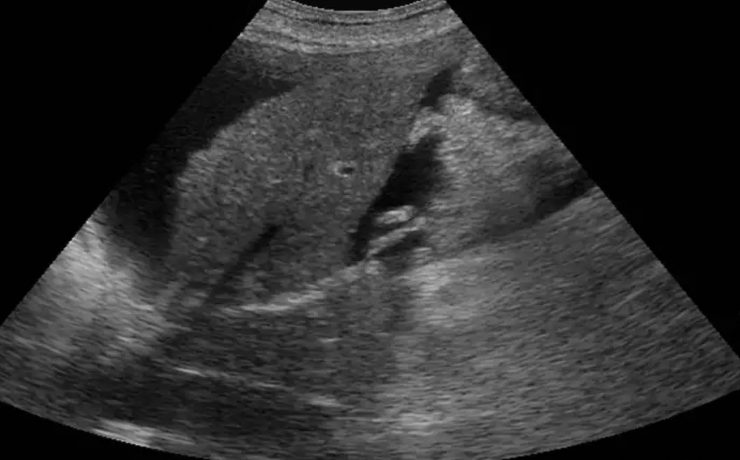

Alteraciones segundo trimestre de gestación.

Objetivo determinar la asociación entre ausencia e hipoplasia del hueso nasal fetal y alteraciones estructurales y/ o cromosómicas en el neonato, en la población en general en el ultrasonido del segundo trimestre. La gran mayoría de malformaciones congénitas no son prevenibles ya que constituyen accidentes en la organogénesis embrionaria y